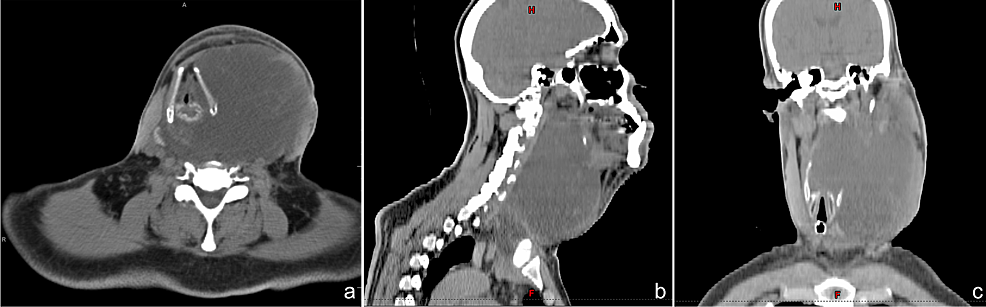

Normal brain,brain tumor,cerebral infarction,intracerebral hemorrhage). Mri scans are very good for looking at the brain and spinal cord and are considered the best way to look for imaging tests such as mri and ct scans may show an abnormal area that is likely to be a brain or spinal cord tumor. Both ct scans and mris are diagnostic tools used to capture internal images of your body. Computed tomography (ct scan) which be directed into intracranial hole products a complete image of the brain.